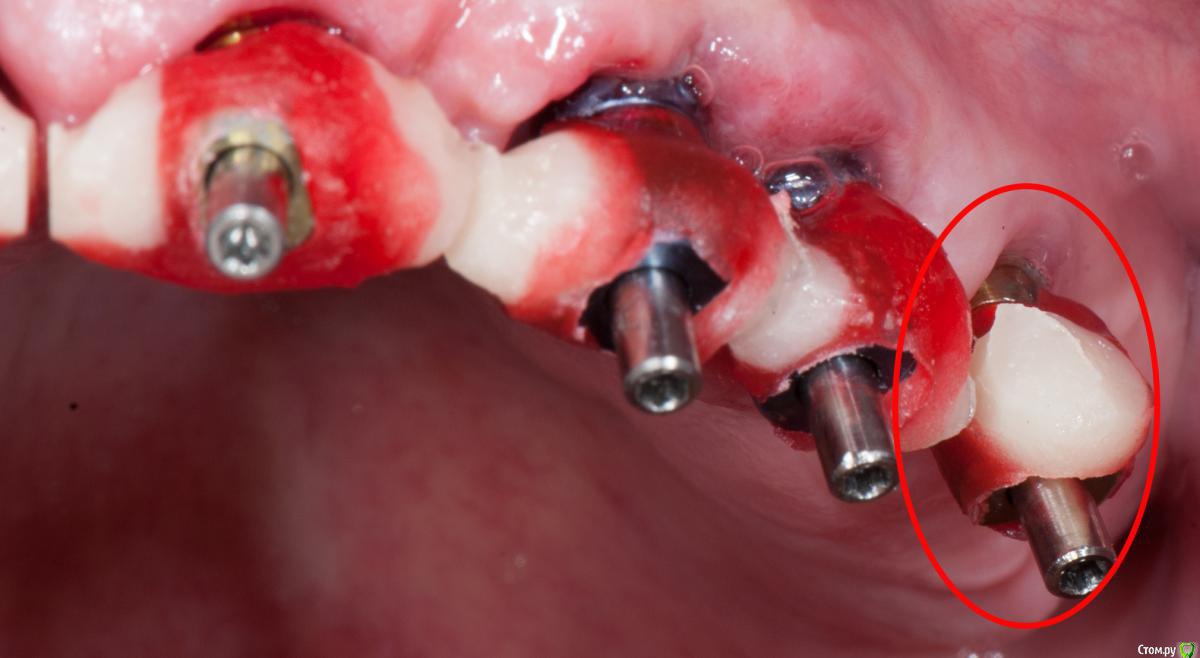

Doc Опубликовано 25 июня, 2017 Поделиться Опубликовано 25 июня, 2017 Не поленился, нашел папочку, в которую старательно складывал такие случаи много лет назад. Сейчас давно уже не было, но тогда, лет десять назад, я каждый случай документировал, чтобы легче было объяснять людям зачем нужен трансферчек. А вот тут уж совсем вопиющий случай, когда техник чебурашку не той стороной засунул в закрытую ложку. С тех пор я только сам лично рассовывал трансферы по слепкам. Ссылка на комментарий